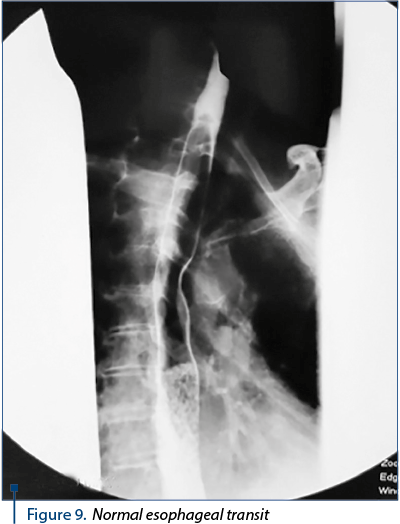

Thirty days of medical care and five days of stopping the drains on the drainage tube are performed, with radiological exploration by oral contrast agent administration. The cervical esophagus of normal appearance, without fistulous traits, was noticed. Minimum stasis in the right pyrimiform sinus. Thoracic esophagus with tertiary contractions in the lower third. Stomach – hypotonic, hypokinetic, with faces, curves and folds of normal appearance.

The success we had with the healing of this serious case has led us to consider the condition of the esophagus and the way of eating naturally within 6 months. The esophageal contrast-transient study revealed the lumen of the esophagus, without the stenosis area, with preserved morphology (Figure 9).

Figure 9. Normal esophageal transit